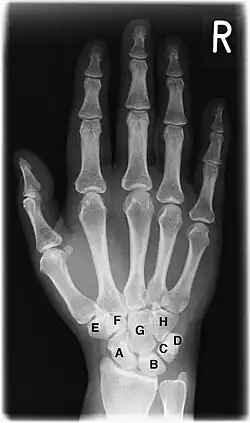

Костный возраст

A Ладьевидная кость (Os scaphoideum)

B Полулунная кость (Os lunatum)

C Трёхгранная кость (Os triquetrum)

D Гороховидная кость (Os pisiforme)

E Кость-трапеция (Os trapezium)

F Трапециевидная кость (Os trapezoideum)

G Головчатая кость (Os capitatum)

H Крючковидная кость (Os hamatum)

Скелет кисти и лучезапястного сустава является наиболее удобным объектом для рентгенологического исследования развития костной системы человека[15]. На рентгенограмме кисти и лучезапястного сустава в прямой проекции видны ядра окостенения костей запястья, дистальных эпифизов лучевой и локтевой кости, наличие синостозирования эпифизов и диафизов. Сроки появления ядер окостенения и синостозирования зависят от пола и от возраста. Методика применяется для определения биологического возраста и его соответствия паспортному возрасту.

У доношенного новорожденного рентгенологическое исследование кисти и лучезапястного сустава в прямой проекции выявляет окостенение диафизов трубчатых костей, (развившееся из основных точек окостенения [или оссификации] начиная со второго месяца внутриутробного развития ребёнка), эпифизы трубчатых костей и кости запястья находятся на хрящевой стадии развития, поэтому на снимке не визуализируются. Иногда на рентгенограмме новорожденного выявляются точки окостенения головчатой и крючковидной костей, что дополнительно подтверждает доношенность новорожденного. В дальнейшем происходит последовательное появление ядер окостенения в костях запястья и эпифизах трубчатых костей. Наступление синостозирования эпифизов и диафизов трубчатых костей у мужчин происходит в возрасте 19—23 года, у женщин в 17—21 год. Современные исследования указывают на более ранние сроки синостозирования (закрытия хрящевых зон роста). Скелет лучезапястного сустава и кисти, состоящий из большого количества костей, претерпевает значительные возрастные изменения. Знание сроков и последовательности появления ядер окостенения позволяет профессионалам определить наличие эндокринной патологии и заболеваний других систем организма[15].